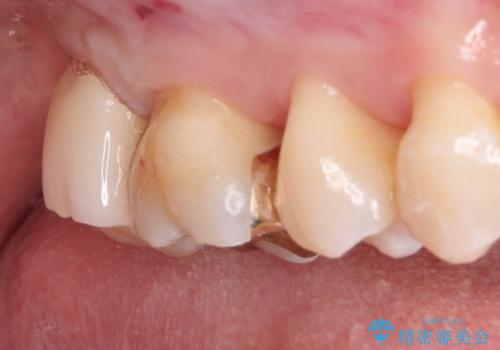

- 虫歯の治療を希望され来院された患者様です。

根管治療を行いオールセラミッククラウンによる治療を行いました。(根管治療は林先生に依頼)

歯肉の下にも虫歯が広がっており歯周外科を行った後、被せもの治療を行いました。